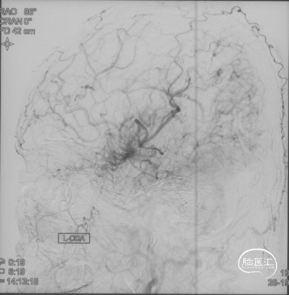

CTA和DSA

CTA和DSA所见:双侧颈内动脉闭塞,右侧椎动脉发出PICA后闭塞,左侧椎动脉V1-V2段闭塞。两条健壮的侧枝通过肌支吻合汇入左椎动脉V2段,构成了整个大脑大部分供血的主要来源。双侧颈外动脉亦有少量血流供应颅内。这样的颅内供血很容易发生失代偿,导致TIA甚至脑梗。